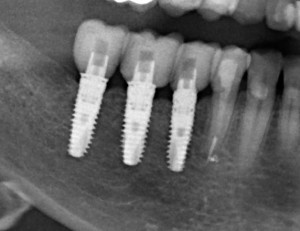

Остеопластика или «наращивание костной ткани» при имплантации — выбор метода и отдаленные результаты.

Cегодня я хотел бы показать вам одну работу, которую я начал более года назад. А заодно рассказать о ее нюансах. Вы знаете, что секретов у меня нет, поэтому буду рад вашим вопросам и ремаркам в комментариях